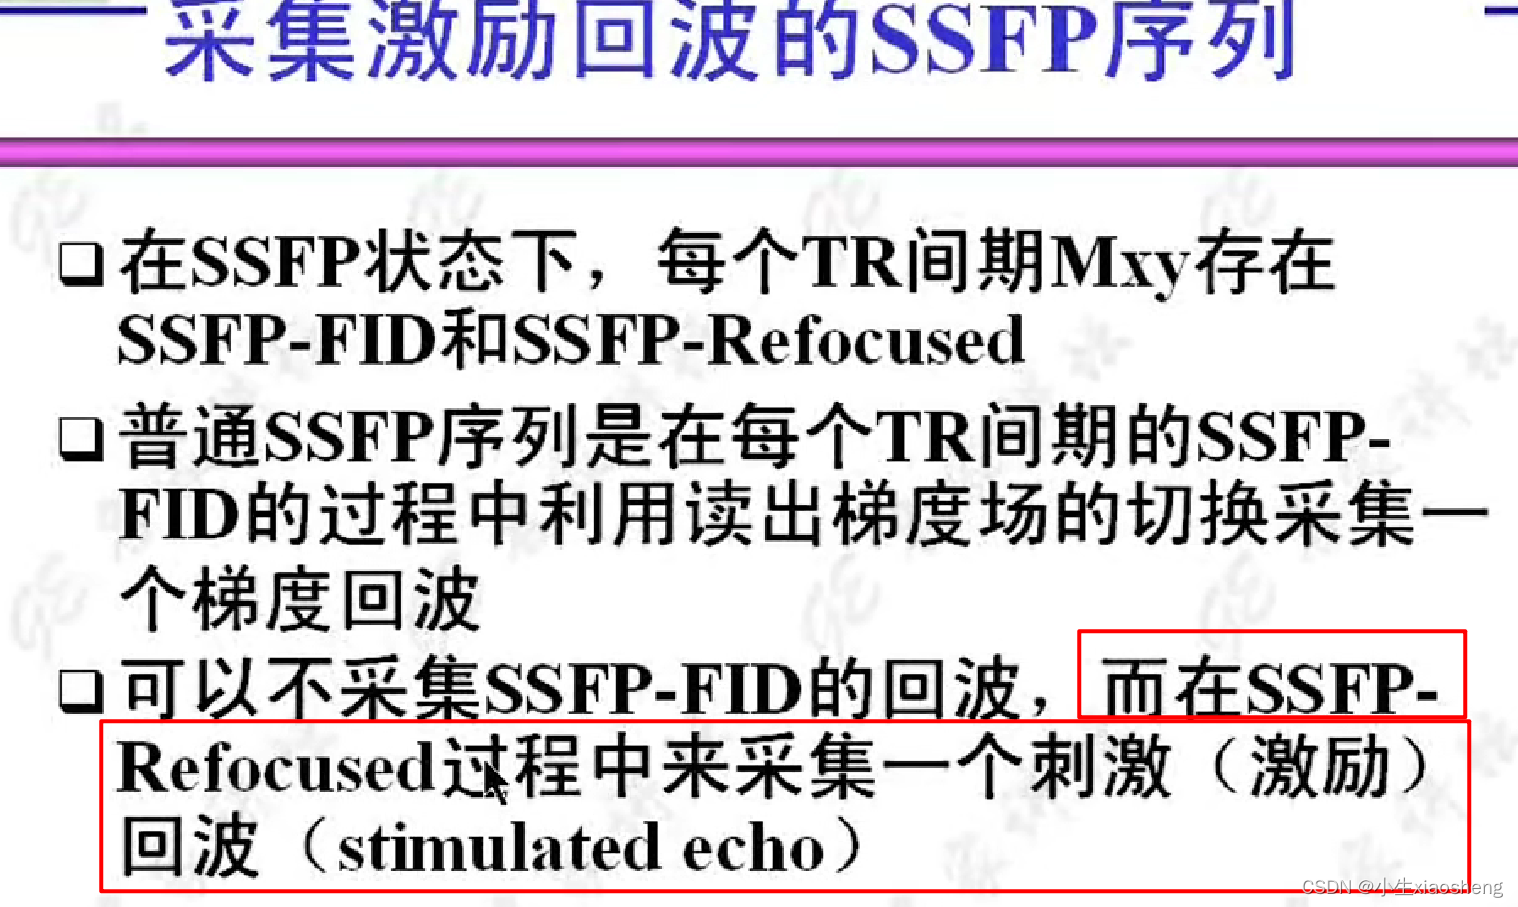

5.采集激励回波的SSFP序列-反

目前GE新型的MRI仪可能不再使用该序列。采波的时候是和上面不一样的。